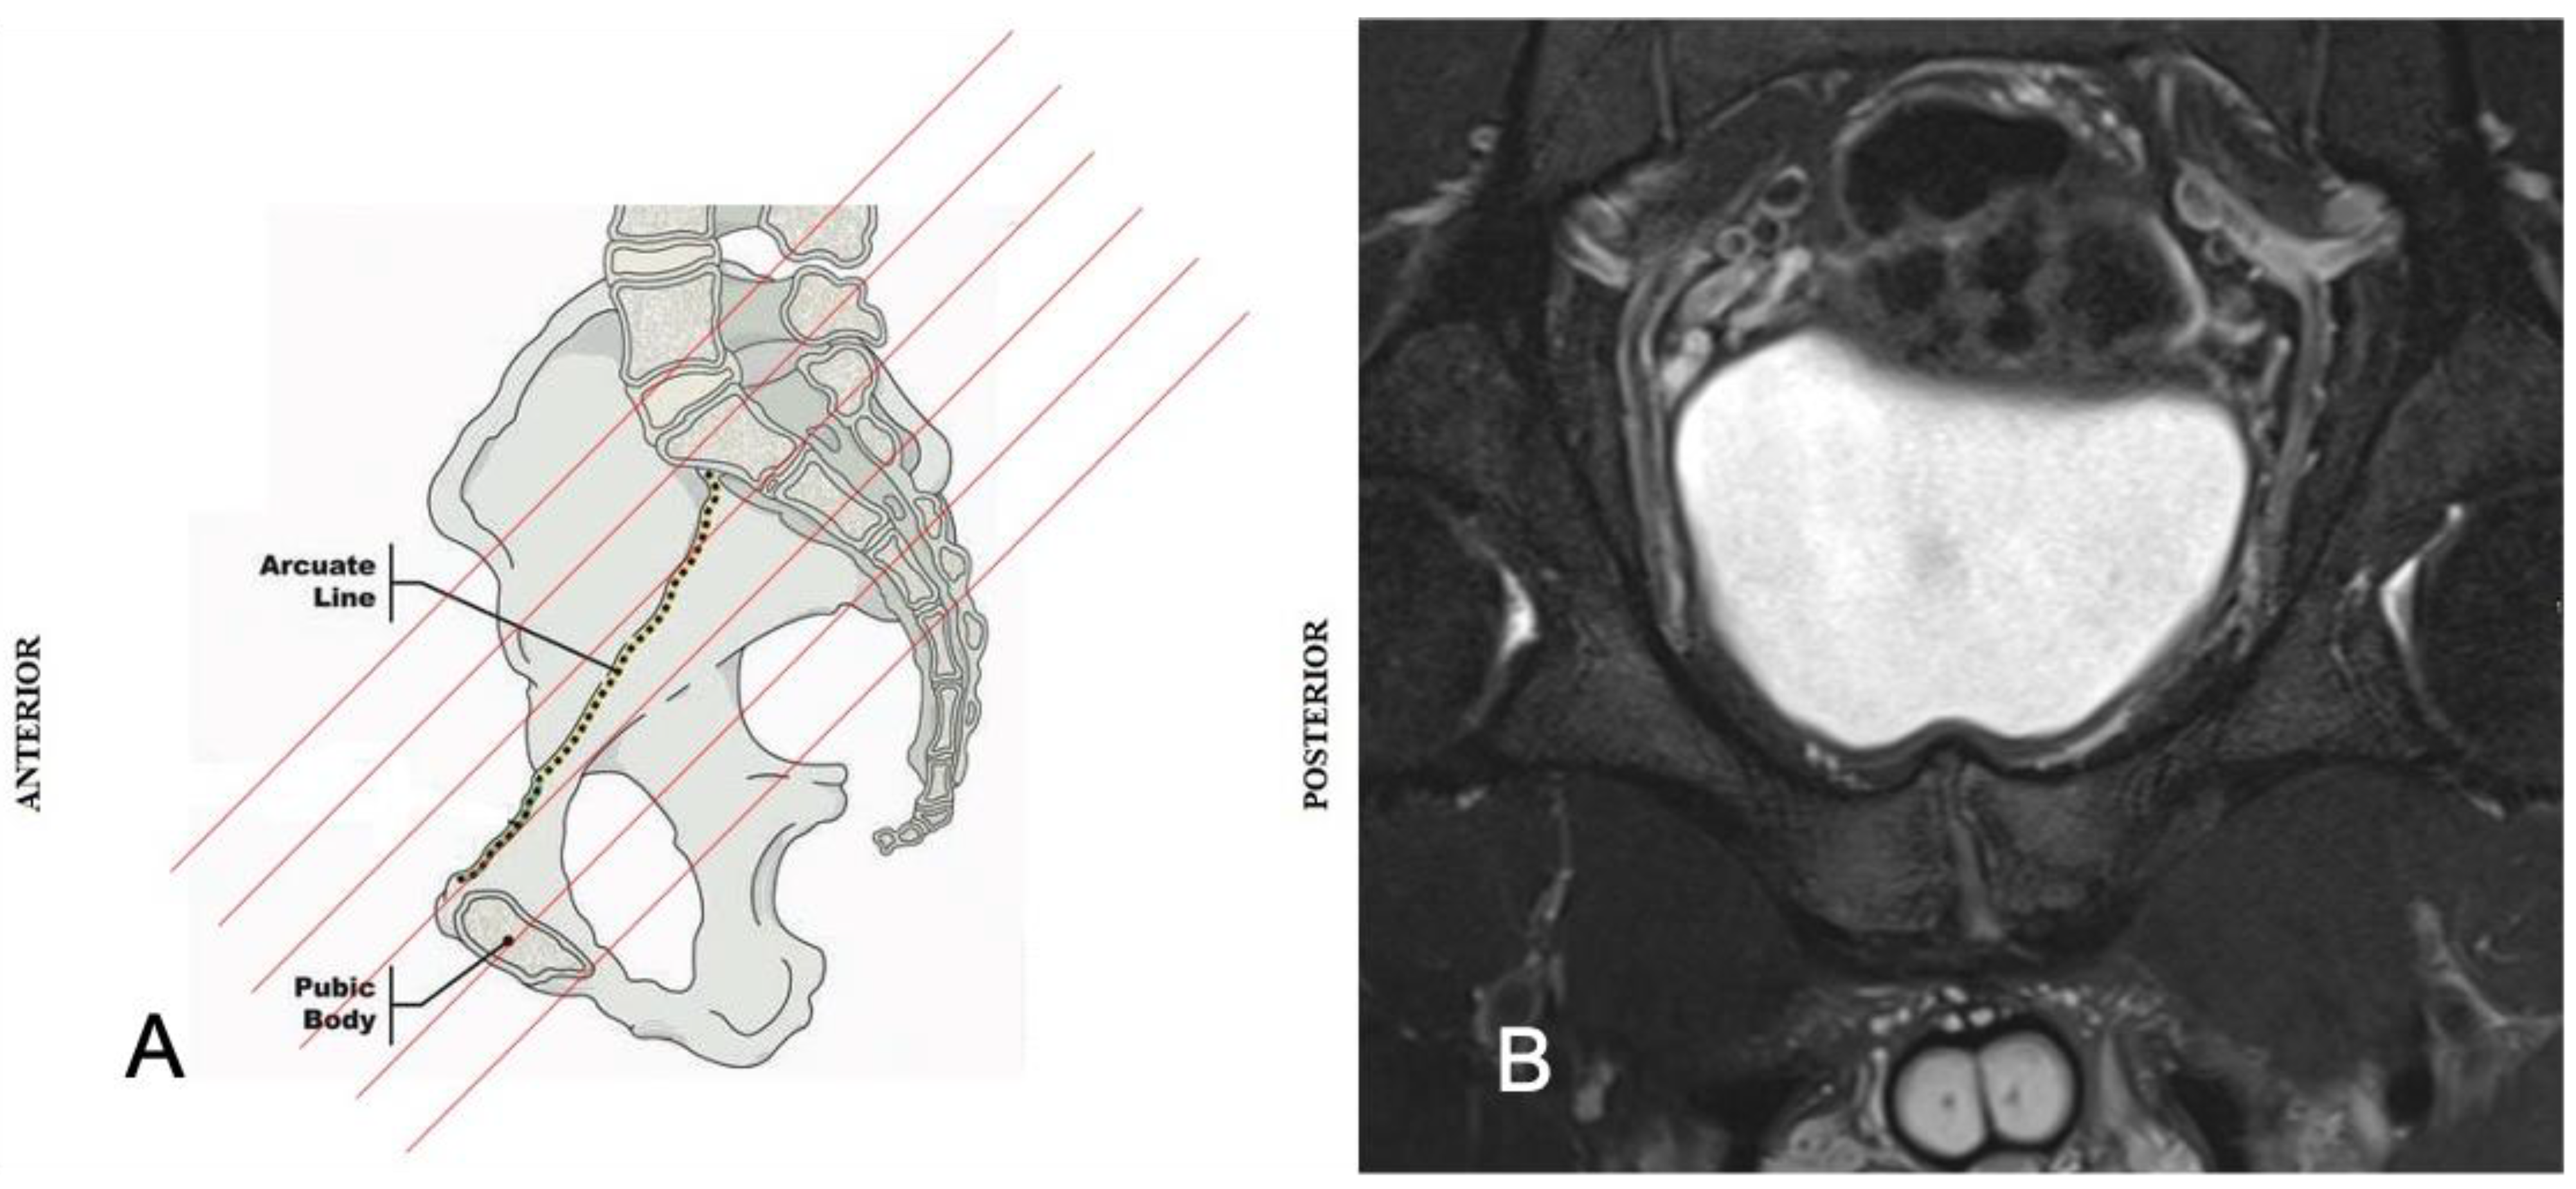

2. Anatomy and Biomechanics of the Pubic Symphisis